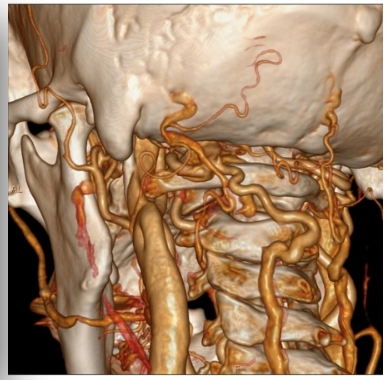

术前颈静脉CTV

通过高分辨率颈静脉超声及CT静脉造影(CTV)检查,清晰显示患者左侧颈静脉存在明确的受压征象,这为脑内异常血流声的产生提供了解剖学依据。为确保诊断的精准无误,在科室的大力支持下,哈医大一院神经外科学科主任史怀璋教授和神经外科三病房主任徐善才教授亲自为患者进行了全脑血管造影(DSA),对检查结果进行研判,并与神经外科二病房主任杨光教授、程玉教授共同分析患者病情。DSA作为血管诊断的“金标准”,进一步证实了颈静脉的受压情况,并排除了其他颅内血管畸形,为后续手术提供了安全保障。在综合所有检查结果并进行详尽的术前讨论后,团队明确诊断患者为“脑鸣综合征”,其根本病因在于颈静脉机械性受压。